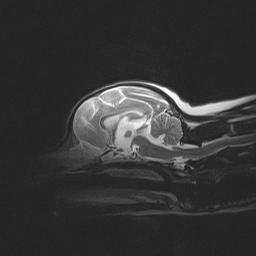

Cognitive dysfunction is a progressive disease with increasing signs of senile behavior. Disorientation is one of the principal symptoms of cognitive dysfunction syndrome. The dog appears lost in the house or yard, gets stuck in corners or under or behind furniture, has difficulty finding the door (stands at the hinge side or goes to the wrong door), doesn’t recognize familiar people, and fails to respond to verbal cues or his name. Activity and sleep patterns are disturbed. The dog sleeps more in a 24-hour period, but sleeps less during the night. There is a decrease in purposeful activity and an increase in aimless wandering and pacing. Dogs with cognitive dysfunction may also exhibit compulsive behaviors with circling, tremors, stiffness, and weakness. House training is another area that suffers. The dog may urinate and/or defecate indoors, sometimes even in the view of his owners, and may signal less often to go outside. There is no specific test for cognitive dysfunction syndrome. The number of symptoms the dog exhibits and the severity of the senile behavior are important considerations in making the diagnosis. An MRI may show some degree of brain shrinkage (as above).